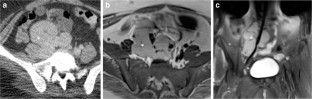

Fig. 1